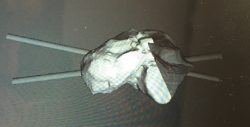

Figura 4. Tallado intraoperatorio con ayuda de la guía 3D.

- Tallado del injerto de manera intraoperatoria (Figuras 4 y 5).